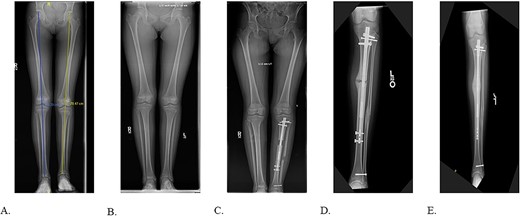

The patient was positioned supine on a radiolucent table with fluoroscopy coming from the contralateral side. The prior infrapatellar scar was incised, revealing bony ingrowth around the proximal end of the implant. A 3.2-mm guide pin was advanced into the center of the implant and a cannulated reamer removed the bony overgrowth. Residual bone surrounding the proximal implant was debrided using a bone curette and then a Nuvasive© conical extractor was attached to the exposed receiving end. The remaining proximal interlocking screw was localized under fluoroscopy and removed. When backslapping the implant, the components disassociated, and the telescopic portion remained lodged in the tibial medullary canal. When consulted intraoperatively, the mother chose to remove all implants by means of tibial osteotomy. An 8 cm long anterior ¼ circumference of the tibia unroofing osteotomy was performed using multiple drill holes and osteotomes (Fig. 2A/B). The remaining portion of the implant was removed with a clamped vice grip and mallet. (Fig. 3A/B). The osteotomy was reduced using a point-to-point reduction clamp and secured with three 2.7-mm lag by technique screws. The wound was irrigated, and 5 cc of demineralized bone matrix was applied to bolster osseous healing.

A: Multi-drill hole technique used to facilitate unroofing osteotomy. B: Completed unroofing osteotomy with visible implant.